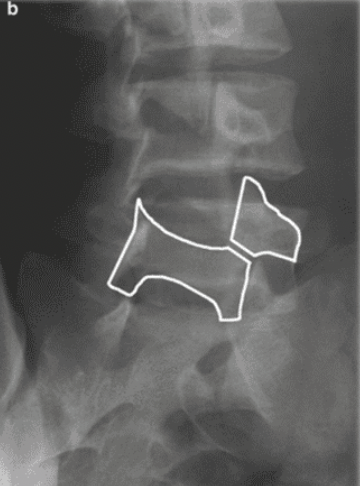

A 17 year old elite gymnast presents to her GP with a 5-month history of lower back pain, which increases in intensity upon hyperextension.

Lateral lumbar-spine x-ray reveals translation of a vertebral body due to a bilateral pars interarticularis fracture.

Which vertebral body and which columns are abnormal?

radiolucent fracture is seen at the pars interarticularis (facet joint) of L4 and L5, causing anterior dislocation (spondylolisthesis) of the vertebral body (L5 in this case)

Middle column: posterior shift at the L5 vertebral level

This would also stretch/displace the anterior longitudinal ligament due to posterior translation in the anterior column

pars interarticularis fracture

pars interarticularis (pars) lies between the superior and inferior articular process at each zygapophyseal/facet joint

usually L5 level

bilateral: spondylolisthesis

unilateral: spondylolysis

spondylolisthesis

bilateral pars interarticularis fracture at the L4/L5 level

disc has slipped posteriorly

stretches/displaces the anterior longitudinal ligament due to posterior translation in the anterior column

spondylolysis

unilateral pars interarticularis fracture

disc has not moved